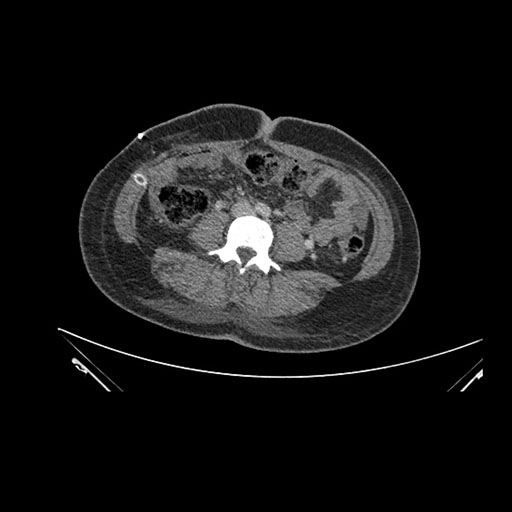

Axial Arterial